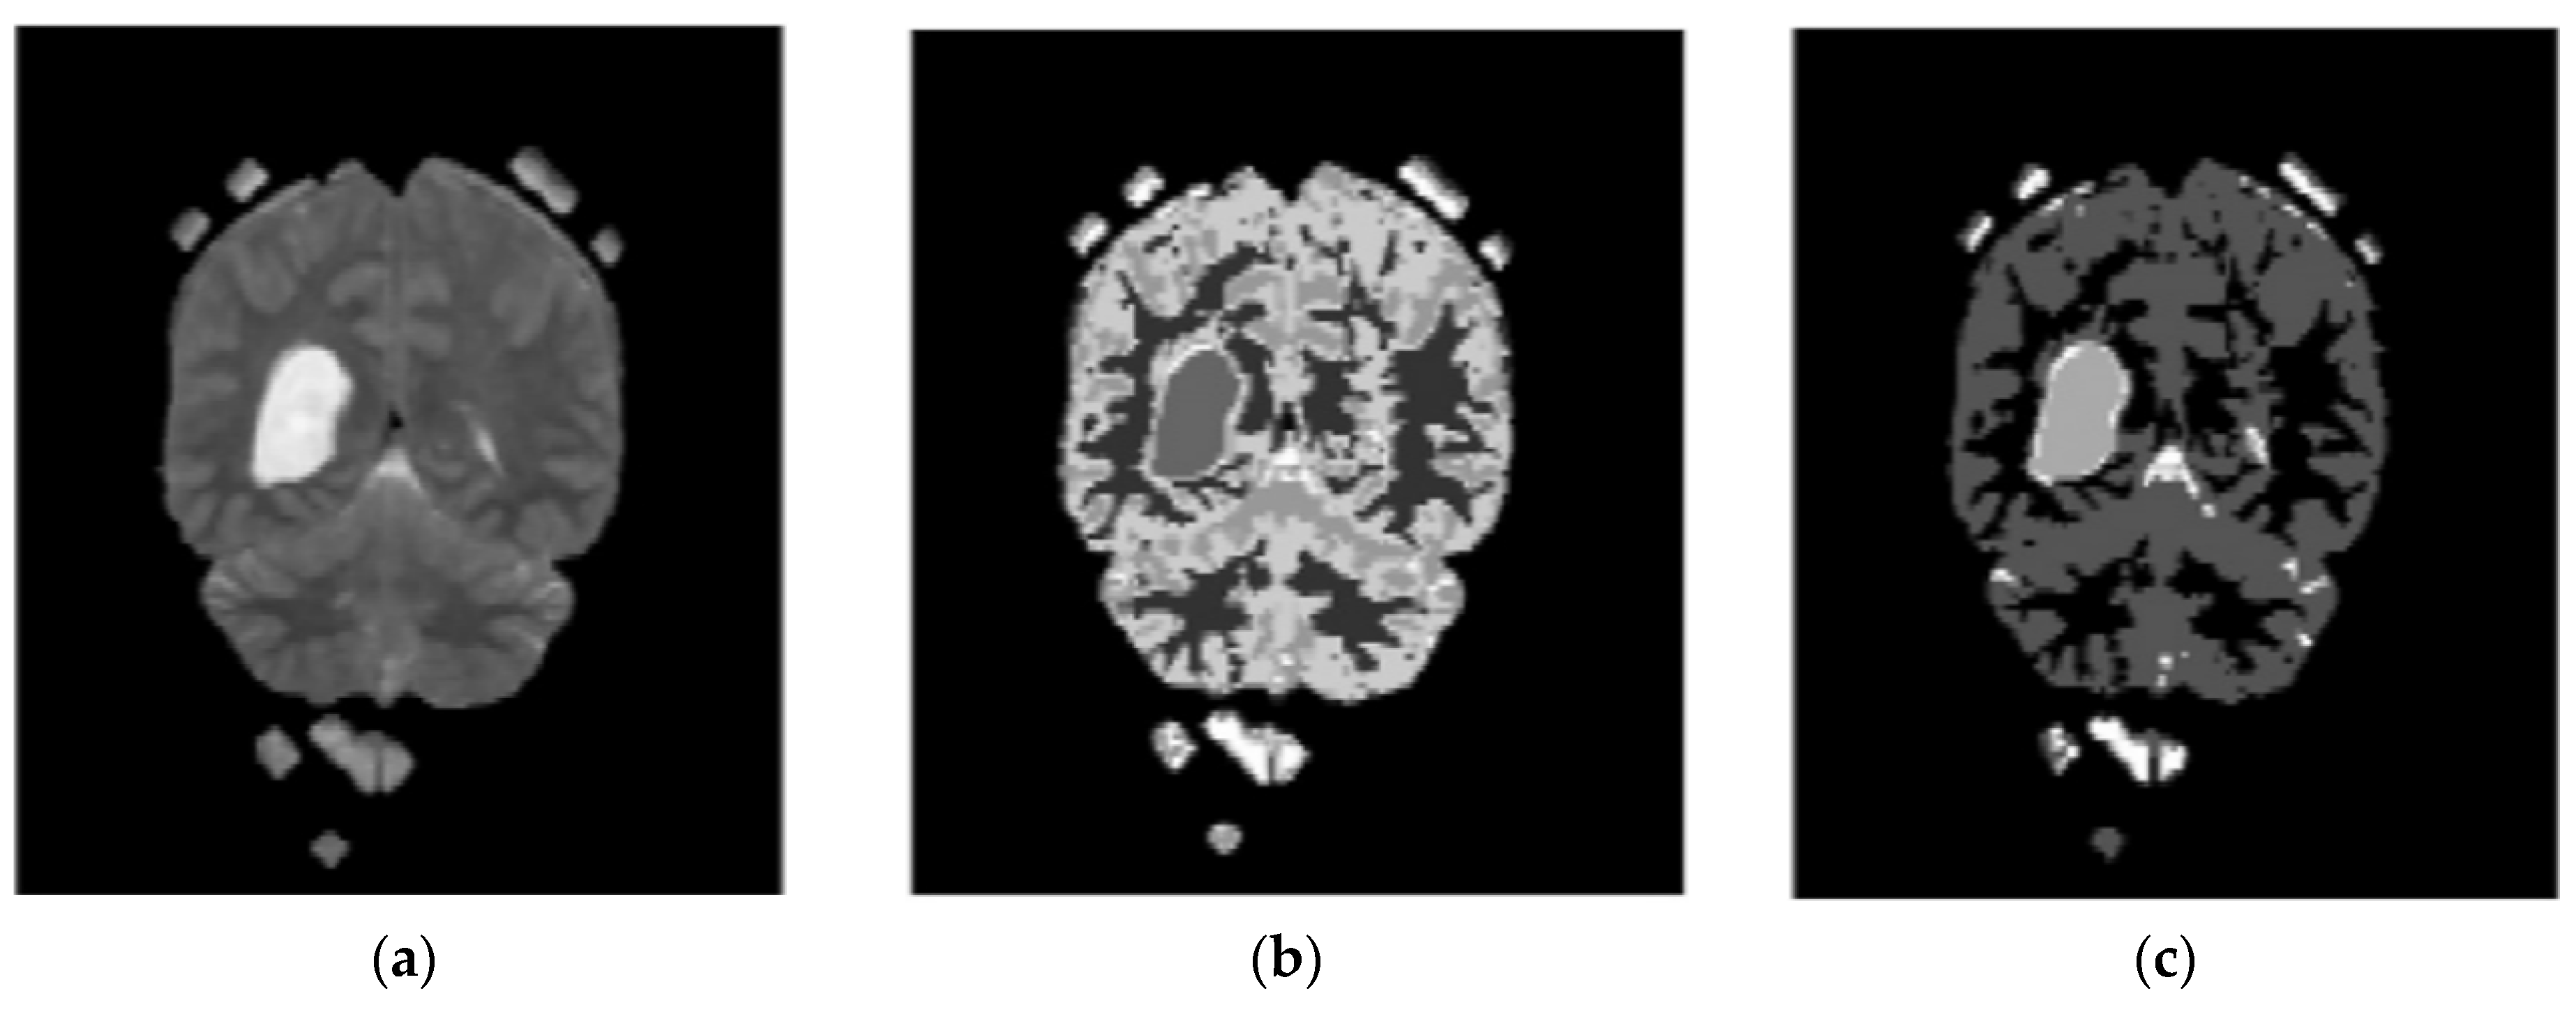

In the proposed segmentation approach, enhanced fuzzy c-means clustering is applied for brain tumor segmentation. In this method, an image’s N pixels are divided into fuzzy c clusters, where c is a positive number and n is a smaller number. Figure 4 and Figure 5 depict various sets of MRI brain images, such as the normal or original image, the binary level image, and the post-morphological operation outcome [37]. The segmentation process is taken as an enhanced version of the fuzzy c-means clustering (EFCMC) algorithm. This includes various stages, as shown in Figure 4 and Figure 5. After performing EFCMC, a final segmented tumor appeared. The proposed segmentation process took less time and was computationally less difficult than other methods.

Figure 4.

Brain MRI images: (a) normal; (b) binary; (c) after a morphological operation.

Figure 5.

Brain images: (a) enhanced; (b) fuzzy c-means 1; (c) fuzzy c-means 2.

An additional set of data was provided in the form of clusters. Alternately, we used a refined version of the fuzzy c-means clustering technique. It is useful for extracting features using LBGLCM and yields decent results when used with segmentation methods.

A total of 620 MRI scans of the brain were analyzed, 612 of which were deemed normal and 8 of which showed signs of tumor growth (abnormal). It took a few stages of the enhanced fuzzy c-means clustering method to get the area of the brain where the tumor was located. The upgraded fuzzy c-means clustering technique was assumed to be used in the segmentation process. There were several steps involved, as seen in Figure 4, Figure 5 and Figure 6. The tumor was successfully segmented after the EFCMC. The proposed segmentation method was faster and required fewer computer resources than other methods. Figure 6 illustrates the brain MRI images, such as the third stage of the enhanced fuzzy c-means cluster impact and it provides the outcome of the segmented tumor region.

Figure 6.

(a) Fuzzy c-means 3; (b) segmented tumor region.